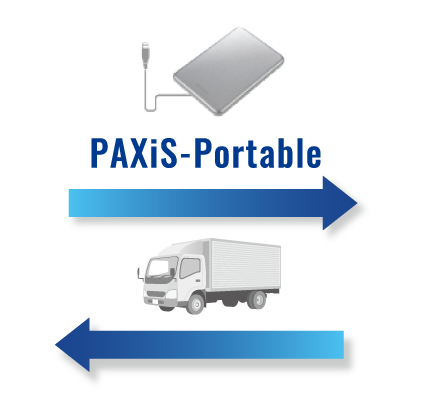

外部読影も簡単にシステム化したい!

- セキュリティ機能付きのメディアを使い、外部でもレポート入力可能

- ネットワークも事前のソフトウェアインストールも不要!手軽に読影開始

- メディアからビューア&レポートが起動し、自宅や勤務先のPCで所見入力

- ネットワーク環境下では、オンラインでのデータ授受も可能

オフラインレポート

データ+システム

(セキュリティ機能付き)

急な医師の交代や、環境の変化にも簡単に対応可能。

外部に多く読影依頼している施設は必見です!